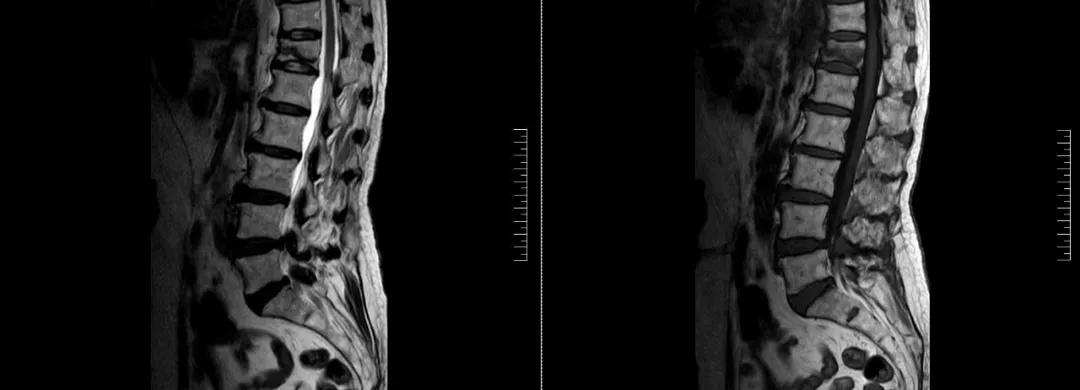

術(shù)前磁共振檢查提示腰1椎體新鮮壓縮性骨折

術(shù)后復(fù)查CT可見(jiàn)骨水泥彌散充分